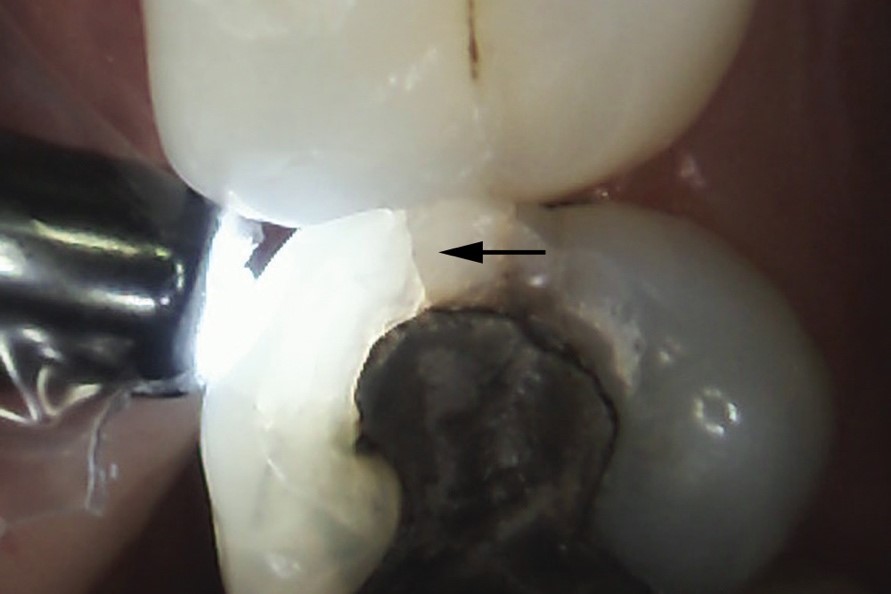

Việc chẩn đoán phân biệt các tổn thương rạn men răng cần phối hợp cận lâm sàng và thăm khám tiền sử bệnh sử. Thông thường, các đường rạn men răng chỉ được phát hiện tình cờ khi thăm khám, không gây cảm giác đau nhức, ê buốt, khó chịu cho bệnh nhân. Phân biệt với các tổn thương nứt vỡ khác bởi tiền sử chấn thương như va đập, ngã….., tiền sử điều trị và các triệu chứng cơ năng. Thăm khám bởi ánh sáng xuyên thấu cho thấy, các đường rạn men răng xuất hiện dưới dạng “vệt tối” nhưng sự xuyên thấu ánh sáng trên bề mặt răng là đồng nhất. Đây là yếu tố chỉ điểm để phân biệt rạn men và các đường nứt, gãy răng thường quy, thường là các đường gãy tiến triển sâu tới ngà và các mô cứng khác.

Tổn thương nứt vỡ răng có tiến triển tới ngà, đặc trưng là sự truyền sáng bị đứt gãy tại đường nứt, khiến bên chiếu sáng hấp thụ hết lượng ánh sáng đơn sắc, trong khi nửa còn lại bên đường gãy lại tối màu hơn |